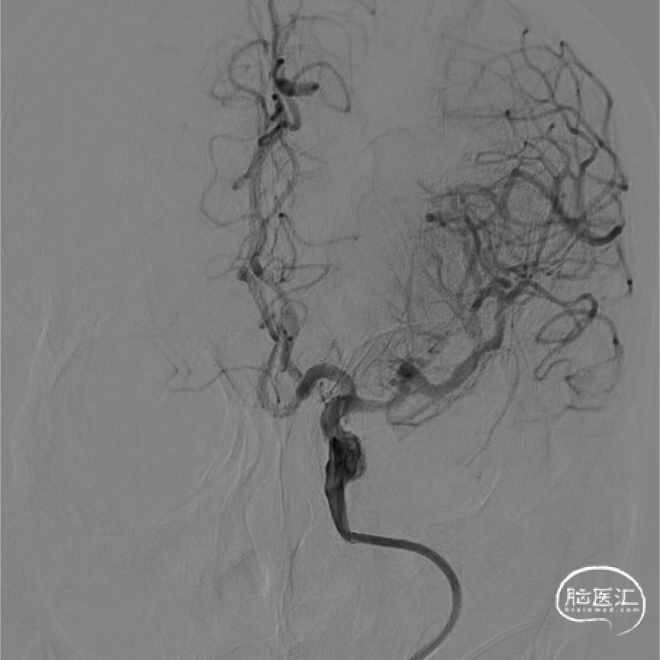

术前DSA造影:

左侧颈内动脉闭塞,血管迂曲明显。

1. 病因评估:术前CT排除颅内出血,CTA提示患者为左侧颈内动脉闭塞所致急性缺血性卒中诊断明确;术前DSA造影证实患者左侧颈内动脉闭塞、前交通动脉开放,闭塞节段较长累及左侧大脑中动脉,提示血栓负荷量大;考虑患者既往房颤病史,血管闭塞断端整齐,突发起病,考虑心源性栓塞性卒中可能性大。

在长鞘支撑下将React™ 71一次性颅内血栓抽吸导管上高至血栓近端,React™ 71一次性颅内血栓抽吸导管到位后行持续负压抽吸。尽管患者血管迂曲,但React™ 71一次性颅内血栓抽吸导管轻松到位。